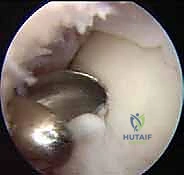

- التنظير التشخيصي للمفصل (Diagnostic Arthroscopy): في بعض الحالات المعقدة، يتم إدخال كاميرا دقيقة (منظار) داخل الكاحل لتقييم الغضروف بالرؤية المباشرة وتقييم مدى صلابته.

1. الاستكشاف والتنظيف: يُدخل الدكتور هطيف الكاميرا الدقيقة لتقييم حجم الآفة بدقة، وتنظيف أي أنسجة تالفة أو أجسام حرة داخل المفصل.